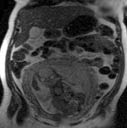

In a pregnant patient, where both the baby and mother are being imaged, other imaging exams, such as ultrasound or magnetic resonance imaging (MRI), that do not involve x-rays are sometimes used.

However, when ultrasound or MRI does not provide the answers needed, or there is a time constraint, CT may be the best imaging option.